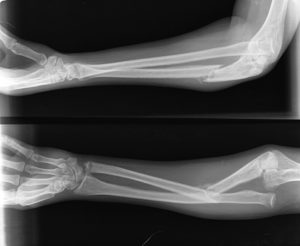

پرتونگاری (X-ray): این یکی از روشهای اصلی تشخیص شکستگی است. پرتونگاری ساعد دست به پزشک کمک میکند تا شکل و موقعیت استخوانها را بررسی کند و هرگونه شکستگی، ترک، یا جابجایی را تشخیص دهد.

درمان شکستگی ساعد با تشخیص دقیق نوع و محل شکستگی آغاز میشود. پزشک پس از معاینه فیزیکی، از تصویربرداری رادیولوژی یا سی تی اسکن برای تعیین شدت آسیب استفاده میکند. بررسی وجود جابجایی استخوان، آسیب به بافت نرم و جریان خون ناحیه ضروری است. در موارد شدید ممکن است تورم یا تغییر شکل واضح دیده شود. تشخیص کامل پایه تصمیمگیری برای انتخاب روش درمانی مناسب است.